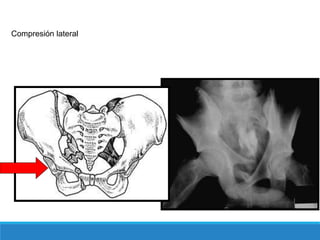

Este documento describe las fracturas de pelvis, incluyendo su etiología, mecanismos, clasificación y tratamientos. Las fracturas de pelvis se clasifican según el sistema de clasificación de Tile, que categoriza las fracturas como Tipo A, B o C dependiendo de su estabilidad y ubicación. El tratamiento depende de la clasificación Tile, con reposo para el Tipo A, estabilización del anillo anterior para el Tipo B, y estabilización anterior y posterior para el Tipo C.